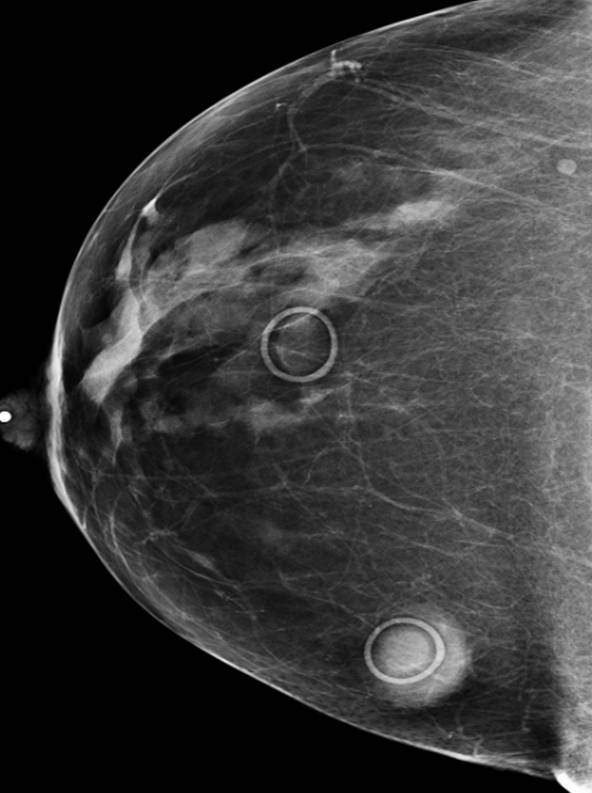

Screening mammograms enhanced by CAD trigger more false alarms than non-CAD screenings and detect more early cancers that may never have needed treatment.

CAD may help highlight nodules the clinician may have otherwise missed, but its use is not without legal ramifications. What do you think? Take this survey.